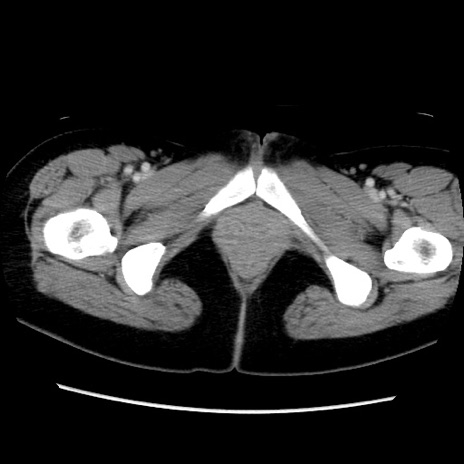

症例39(横断像)

【症例】40歳代女性

【主訴】上下腹部痛

【現病歴】2日目から下腹部痛あり。夜間は痛みで眠れなかった。昨日より上腹部痛と下痢が出現。臥位で痛みは軽快したため、休んでいた。本日になって臥位でも立位でも痛みが強くなってきたため救急要請。

【既往歴】子宮内膜症

【身体所見】部:平坦・軟、左上下腹部に圧痛あり、反跳痛あり。

【データ】WBC 21800、CRP 26.78